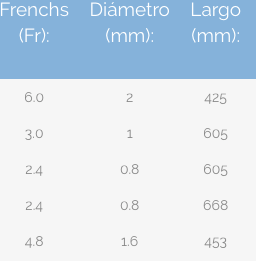

Nefrolitotomía Percutánea Con técnica Miniperc

Miniperc, es una técnica eficaz y segura, con una mínima incisión en la piel, para el tratamiento de las piedras en el riñón de pequeño y mediano tamaño.

El riesgo de sangrado, las posibles complicaciones y el tiempo de hospitalización es menor que con otras técnicas de nefrolitotomía percutánea.

Los calibres de los tractos de acceso se alejan considerablemente del calibre de la cirugía percutánea clásica, disminuyendo asi los daños generados en el parénquima renal.

El nefroscopio minipercutáneo es recomendable para el tratamiento de piedras de 1 hasta 3 cm, tiene un canal de trabajo que permite el paso de instrumentos de hasta 6.7 french.

Su diseño compacto y la ventaja de realizar incisiones mas pequeñas permiten una recuperación mas rápida y la reducción de complicaciones postoperatorias.

Tras la incisión cutánea, se ensancha el acceso con un solo dilatador hasta el punto de que la vaina se pueda deslizar hasta el riñón, ya no es necesario recurrir a los dilatadores telescópicos o los dilatadores de varios tamaños.

La miniperc implica, además de la reducción del diámetro del tracto externo y del instrumento de trabajo (nefroscopio), otras modificaciones en la técnica de la litotricia en beneficio de la comodidad postoperatoria del paciente.

Entre estas modificaciones se encuentran el uso de tecnología láser para la fragmentación o pulverización de cálculos, la disminución de los elementos de extracción, la reducción del calibre de la nefrostomia (abertura desde el exterior del cuerpo hasta la pelvis renal) y diferente estrategia de salida.

Nefroscopio

Telescopio Panoview con ocular desplazado lateralmente, dirección de visión de 12° y canal de trabajo de 6 Fr.